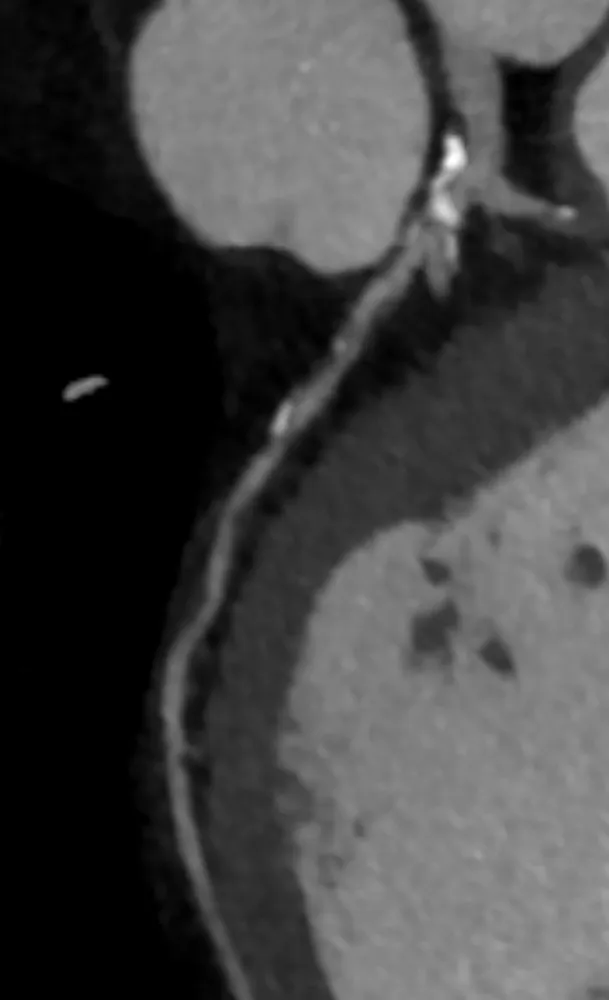

Die Beurteilung des Stenosegrads erfolgt auf Grundlage der luminalen Einengung. Eine Stenose > 50 % wird als potenziell hämodynamisch relevant eingeschätzt. Zur Beurteilung der funktionellen Relevanz kann bei Bedarf eine CT-basierte Bestimmung der fractional flow reserve (FFR-CT) oder eine weiterführende Ischämiediagnostik erfolgen (Abb. 3).

Ergänzend liefert die Stress-Kardio-Magnetresonanztomographie (MRT) wertvolle Informationen zur myokardialen Perfusion. Sie erlaubt eine funktionelle Beurteilung ischämischer Areale ohne Strahlenexposition. Die Kombination aus struktureller (CCTA) und funktioneller (MRT) Bildgebung bietet eine umfassende Risikoeinschätzung mit hoher Sensitivität und Spezifität.